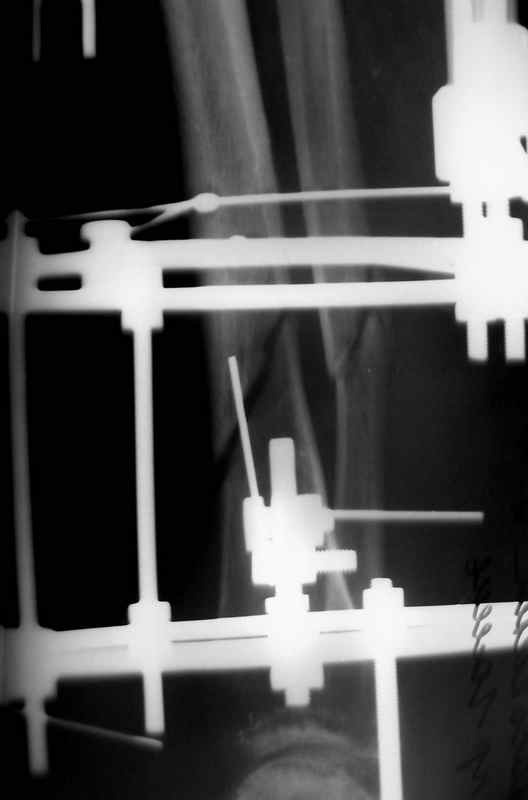

Псевдоартроз, краевой дефект

Больная 54 года, 5 м. назад открытый оскольчатый перелом 2-3 тип, Первично ЧКДО, открытое ведение раны, при этапных некрэктомия " ушел" осколок внутренней стенки б/бецовой кости, 7 сутки пластика м/тканями ,вторичные швы.

Контакт отломков только по спирали наружной стенки,заживление раны полное, на 3-4 месяце ЧКДО воздействие на регенерацию микродистрациями , 5 месяц снят аппарат по причине нестабильности и реакции м/тканей. В данный момент проблем с тканями нет, на Р-граммах псевдоартроз, клинически подвижность,больная ходит в ортезе с дозированной нагрузкой.Местно рубцовый процесс 3х5 в зоне перелома.

Готовится к операции.

Планы

1. Только штифт первично динамизированный Достаточно-ли кантакта для сращения?

2.Аддаптирующая резекция через небольшой разрез вне рубца, с оставлением костных фрагментов парадифизарно, как элемент костной пластики, штифт с динамизацией первично (возможно, на начальном этапе + 2 кольца ЧКДО с отсрочкой дистального блокирования)с последующей компенсацией укорочения транспортом на штифте.